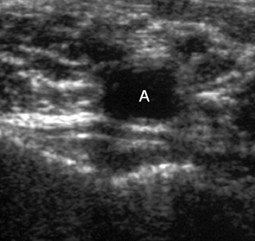

Abb. 3